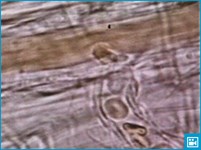

Диаметр отдельного эритроцита равен 7, 2-7, 5 мкм, толщина — 2, 2 мкм, а объем — около 90 мкм3. Общая поверхность всех эритроцитов достигает 3000 м2, что в 1500 раз превышает поверхность тела человека. Такая большая поверхность эритроцитов обусловлена их большим числом и своеобразной формой. Они имеют форму двояковогнутого диска и при поперечном разрезе напоминают гантели. При такой форме в эритроцитах нет ни одной точки, которая бы отстояла от поверхности более чем на 0, 85 мкм. Такие соотношения поверхности и объема способствуют оптимальному выполнению основной функции эритроцитов — переносу кислорода от органов дыхания к клеткам организма.

Эритроциты переносят кислород от легких к тканям и двуокись углерода от тканей к органам дыхания. Сухое вещество эритроцита человека содержит около 95% гемоглобина и 5% других веществ — белков и липидов. У человека и у млекопитающих животных эритроциты лишены ядра и имеют форму двояковогнутых дисков. Специфическая форма эритроцитов обусловливает более высокое отношение поверхности к объему, что увеличивает возможности газообмена. У акул, лягушек и птиц эритроциты овальной или округлой формы, содержат ядра. Средний диаметр эритроцитов человека 7-8 мкм, что приблизительно равно диаметру кровеносных капилляров. Эритроцит способен «складываться» при прохождении по капиллярам, просвет которых меньше диаметра эритроцита.